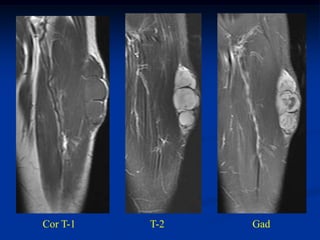

Cor T-1   T-2   Gad

Sag T-1

Gad

Axial T-1   T-2